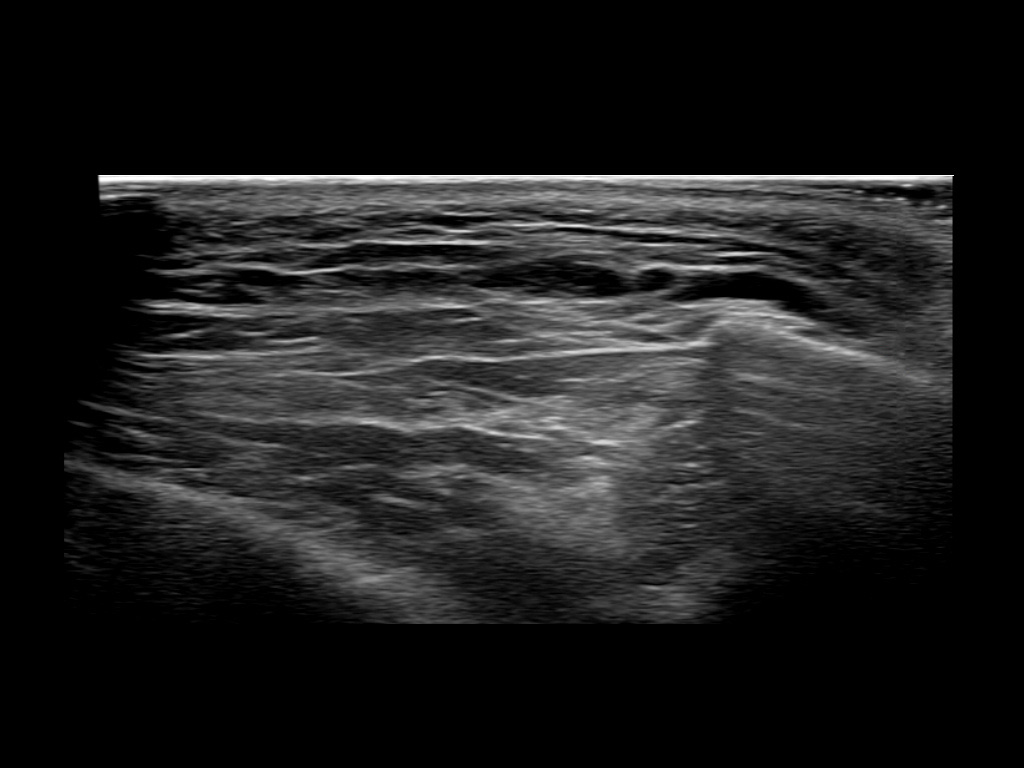

Study the first image to recognize the different layers. If you are sure about the layers, swipe to the second image to view the answer (if applicable).